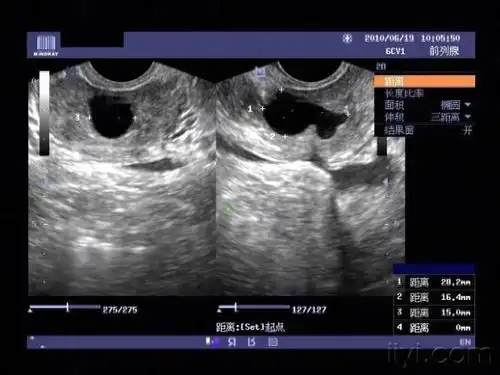

精囊腺囊肿 - 泌尿及生殖医学专业讨论版 - 爱爱医医学论坛

典型——精囊腺囊肿!欢迎参与前列腺钙化与结石的讨论! - 超声医学讨